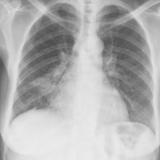

Case 2 Lateral